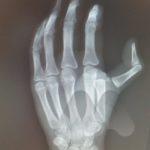

Dislocations are commonly a result of trauma causing the joint to move out of its normal position and relationship with other bones. Dislocations can be accompanied by fractures. Sometimes the dislocation causes an obvious deformity and can be pulled or pops back into position on it’s own. In some situations, the joint cannot be pulled back into position or keeps falling out of position due to tissues such as bone fragments blocking the reduction or due to torn ligaments or fracture through supporting bones. In this situation, you may need to have some form of anaesthetic to realign the bones in the Emergency department or operating theatre or in some cases, the joint being opened and surgically stabilised.